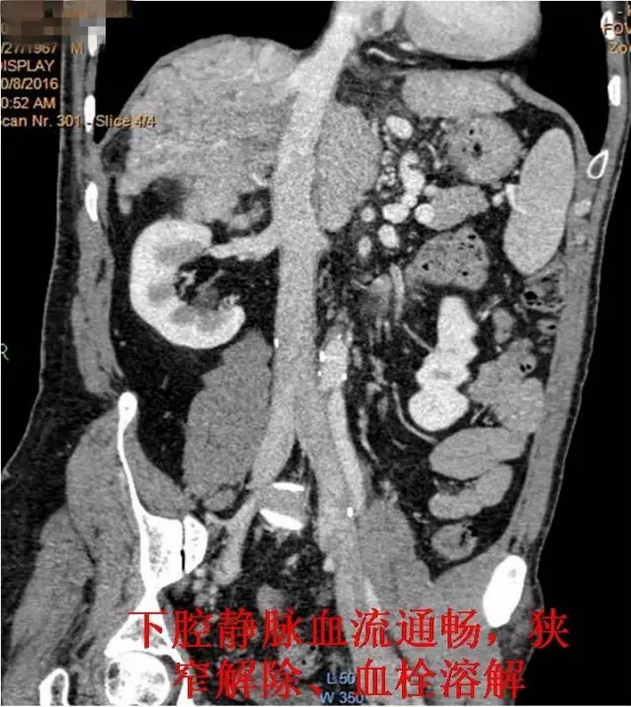

术后复查CTV

入院后王兵副院长热情接待了郑先生,经过检查怀疑其患上一种罕见的“布加综合征”,经进一步检查,结果证实了判断,明确患者所患疾病为“布加综合征”,而非单纯的“下肢静脉曲张”。同时发现患者合并有下腔静脉(一条通往心脏的大血管)血栓形成。经过科内分析讨论,王兵副院长决定为患者行介入微创治疗。经过详细的术前评估及周密的术前准备,王兵教授带领血管外科崔文军副主任、司江涛主治医师、李攀峰医师为郑先生施行了手术。在局部麻醉下穿刺股静脉后,首先巧妙的在下腔静脉内置入血栓过滤装置,预防血栓脱落导致肺栓塞,然后放置溶栓导管,经导管泵入溶栓药物溶解血栓,待患者血栓溶解后,给予置入球囊扩张导管充分扩张患者下腔静脉重度狭窄处,成功解除下腔静脉狭窄。术后患者下肢皮肤溃疡很快愈合,腹部迂曲扩张的血管消失,手术效果满意。